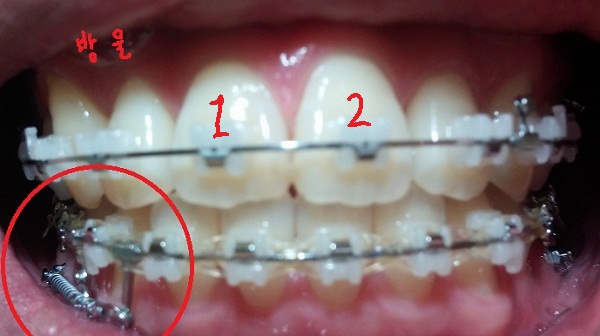

치료내용

-하악 파워체인 엇갈려서 걸어놓기(후기 23화와 같은 치료),

-하악 스프링 + 덧대기(잇몸이 눌리지 않게)

-고무줄착용하기(전 치료와 동일)

현재 교정진행상태

-중심선 99% 맞은 상태!!

-하악 파워체인으로 치아끼리 꽉 조여서 마무리로 가는 중!!

-일회용 고무줄로 치아를 다물 때, 뜨는 공간이 없게

상악 송곳니와 하악 송곳니를 당기는 중!!

[스프링 정면]

[고무줄 정면]

[고무줄 왼쪽]

[고무줄오른쪽]